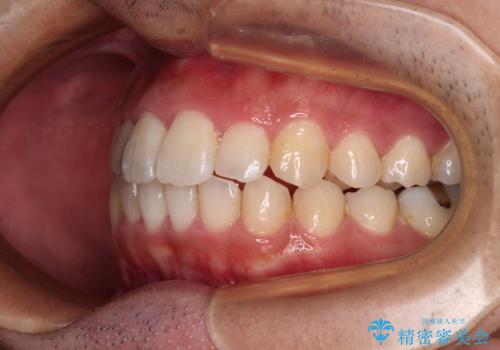

前歯のデコボコと突出感をマウスピース矯正できれいに

- 上下前歯のデコボコと突出感を気にして来院された患者様です。

目立たない装置を希望されたため、インビザラインによるマウスピース矯正を行うこととしました。